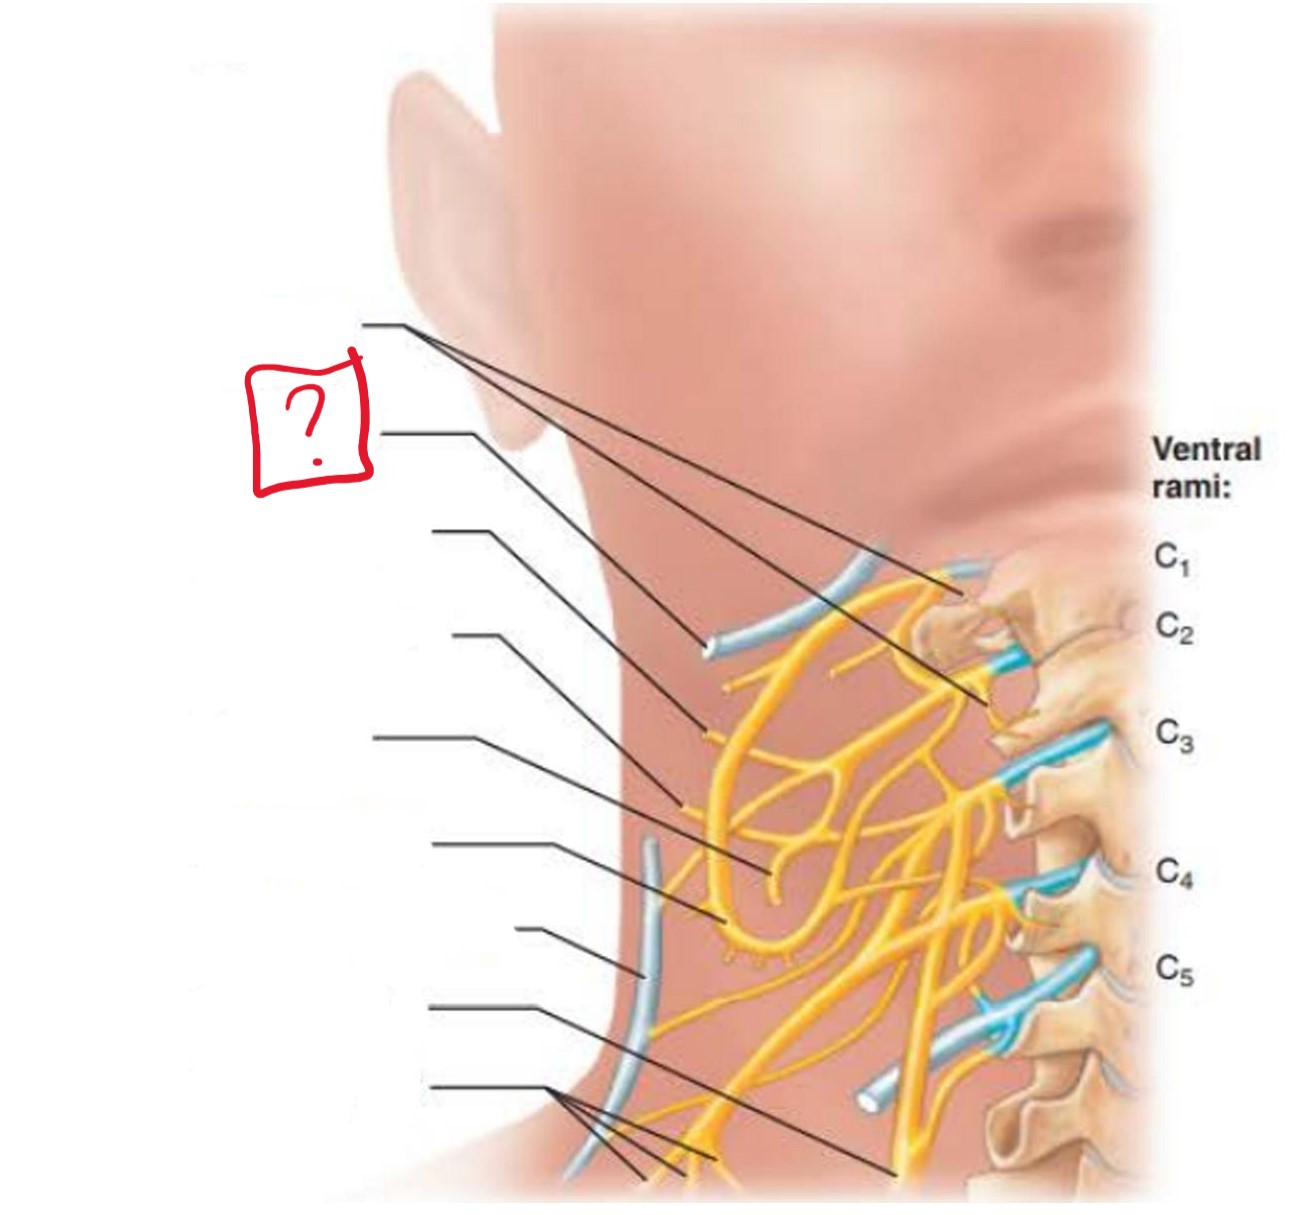

cervical plexus

C1-C4

segmental branches

hypoglossal nerve (12)

lesser occipital nerve

greater auricular nerve

transverse cervical nerve

ansa cervicalis

accessory nerve (11)

phrenic nerve

supraclavicular nerves